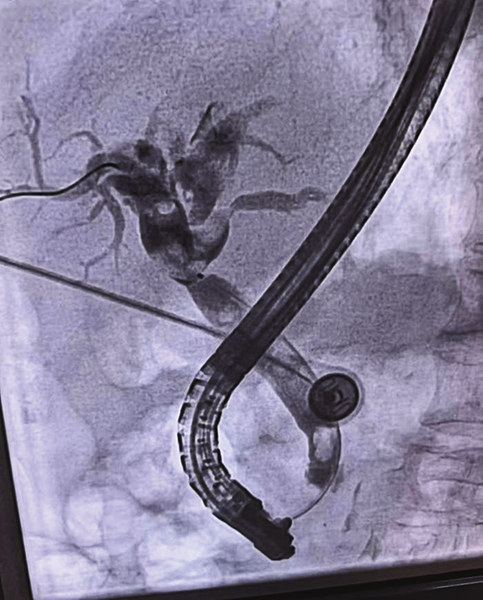

近日,在消化内科二病区,80岁的戚奶奶(化名)因胆道梗阻引发食欲缺乏、尿黄,生命健康亮起红灯,消化内科团队凭借精湛的ERCP(经内镜逆行胰胆管造影)技术,成功解除了危机,再次印证了科室在高龄患者内镜治疗领域的过硬实力。

患者入院后,消化内科二病区主任成波立即组织团队进行病例讨论,最终决定采用ERCP技术为其实施微创治疗,最大程度降低手术创伤,更适合高龄患者。

对于高龄患者,内镜治疗的难点在于既要保证操作精准,又要严格控制风险,这对团队的技术熟练度和应急处理能力都是极大的考验。近年来,科室不断精进ERCP技术,已成功为多名80岁以上高龄患者解决了胆道结石、胆道狭窄、急性胰腺炎等消化科“疑难杂症”,手术成功率始终保持在较高水平。从术前详细评估患者基础疾病、制定个性化方案,到术中精细化操作、实时监测生命体征,再到术后专业护理、预防并发症,科室构建了一套全流程的高龄患者诊疗保障体系,让更多老年患者无需承受开腹手术的痛苦,快速恢复健康。